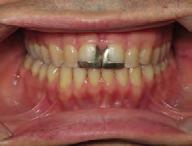

Clinical evaluation showed a mild Class III skeletal pattern with a constricted maxilla, mildly dolichofacial and straight

profile (Figure 1). Full adult dentition was present with all third molars extracted. Maxillary and mandibular incisors were normoclined. The maxillary midline coincided with the facial midline, and the mandibular midline was 2 mm to the right of the facial midline. There was a 2 mm to 5 mm lateral open bite on the right side from the second molar to the lateral incisor, and the maxillary occlusal plane was canted to the left of the interpupillary line. A lateral tongue thrust into the open bite was noted on swallow.

The right side was in posterior crossbite and there was an edge-to-edge anterior bite with wear on the maxillary central incisors. Mild gingival recession was noted, but soft tissue was generally within normal limits. CBCT analysis found no radiographic evidence of osteoarthritis in the TMJ joints, nor osseous or apical pathology involving the maxillary or mandibular teeth. His airway was not constricted. Initial report from the myofunctional therapist indicated that the patient never developed a mature swallow sequence and had a bilateral posterior tongue thrust.

Figure 1. Initial records.